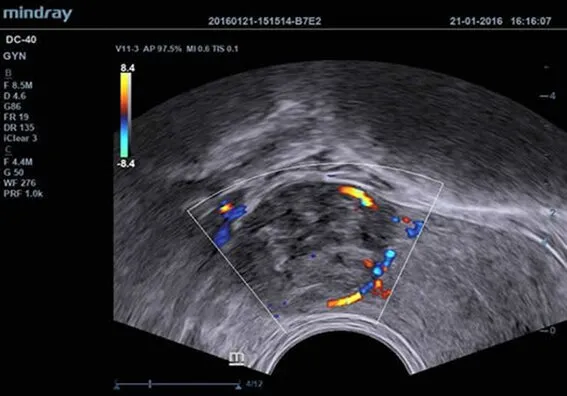

Клинические изображения

| V11-3 | Микроконвексный внутриполостной датчик для гинекологии, акушерства, урологии |